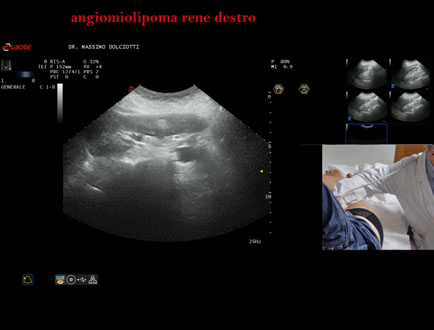

Età Paziente: M 65 anni

Motivazione dell'esame: follow up x angiomiolipoma renale destro.

Commento all'esame: le immagini ed il video documentano il rene destro ptosico, di ecostruttura disomogenea per evidenza in sede corticale polo inferiore di immagine iperecogena, delle dimensioni di 26 x 19 mm, da ricondurre, come prima ipotesi, ad angiomiolipoma. Il rene sinistro è ptosico, di ecostruttura disomogenea per evidenza in sede mesorenale corticale di immagine iperecogena, delle dimensioni di 10 mm, da ricondurre, come prima ipotesi, ad angiomiolipoma.

Conclusioni: grande angiomiolipoma al rene destro e piccolo angiomiolipoma al rene sinistro (large angiomyolipoma in the right kidney and small angiomyolipoma in the left kidney).

Presentazione: Dr. Massimo Dolciotti - Ancona

Elaborazione digitale: Andrea Dini - Ancona